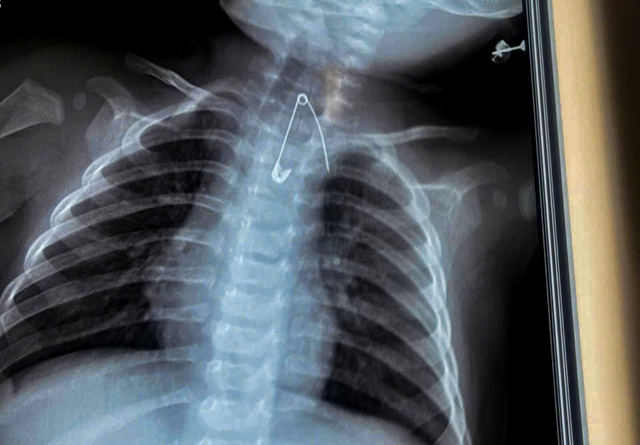

A safety pin was swallowed by a seven-month-old infant from Ca Mau Province in southernmost Vietnam and found lodged dangerously close to the aorta. Photo: Supplied

The second case involved a seven-month-old baby boy, identified as D., also from Ca Mau.

He was brought to the hospital with a two-day history of fever, coughing, and wheezing.

Medical history showed that over the previous three months, the infant had repeatedly suffered from respiratory infections.

Relatives told doctors that the family had a habit of attaching a good-luck charm to the baby's clothing using a safety pin.

Clinical and imaging examinations revealed that the safety pin had migrated into soft tissue and was lodged in an extremely dangerous position near the aorta.

Doctors warned that the sharp object could have caused massive bleeding and posed an immediate threat to the child's life.

Surgeons intervened promptly and successfully removed the safety pin without complications, preventing potentially fatal consequences.